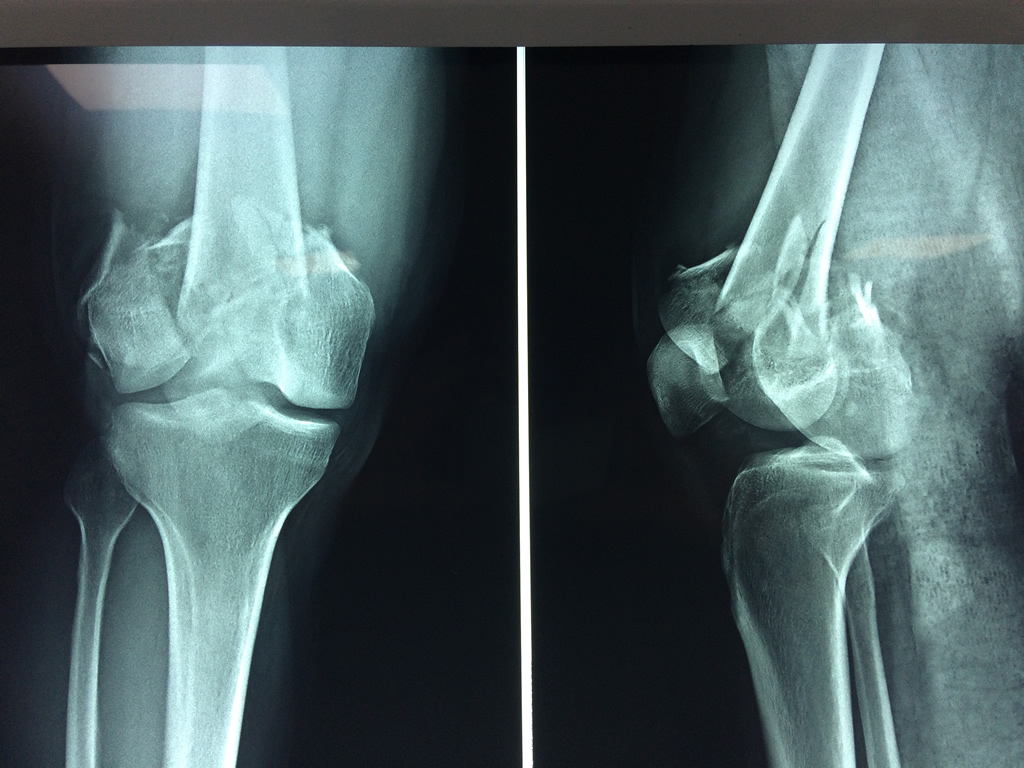

El fémur es el hueso del muslo, el segundo segmento del miembro inferior. Es el hueso más largo, fuerte y voluminoso del cuerpo humano.